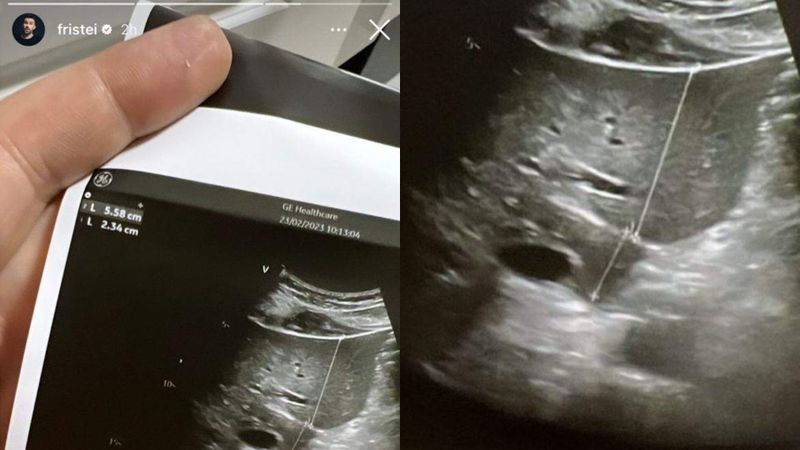

Florin Ristei și Naomi Hedman trăiesc o frumoasă poveste de dragoste. Cei doi s-au cunoscut pe platourile de filmare ale concursului „X Factor”, unde el era jurat, iar ea concurentă. De atunci, sunt de nedespărțit. Cântărețul a publicat o imagine cu o ecografie a unui bebeluș pe rețelele sociale, unde a pus și un mesaj emoționant, care dovedește că abia așteaptă să fie tată.

„Oh my God (n.r.

Oh, Dumnezeule)”, a scris Florin Ristei pe contul lui personal.